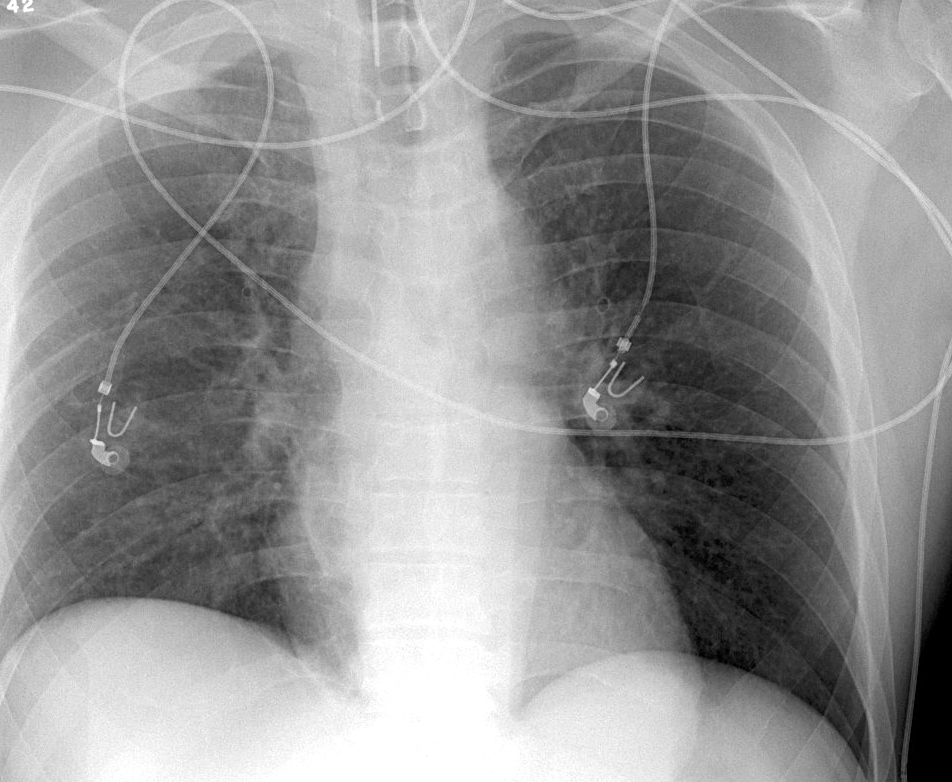

Gallery Blunt Chest Trauma Spine trauma Spine 4a

Spine 4a